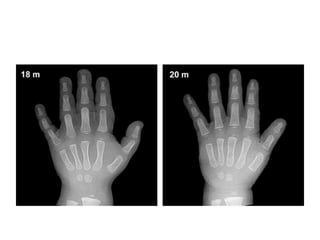

Toddlers

• Males: 14 months to 3 years of age

• The ossification centers for the epiphyses of all

phalanges and metacarpals become

recognizable during this stage, usually in the

middle finger first, and the fifth finger last.

• Bone age determinations are primarily based on the assessment

of the number of identifiable epiphyseal ossification centers,

which generally appear in an orderly characteristic pattern, as

follows

• 1) Epiphyses of the proximal phalanges;

• 2) Epiphyses of the metacarpals;

• 3) Epiphyses of the middle phalanges; and,

• 4) Epiphyses of the distal phalanges.

• The number and degree of maturation of the carpal bones in

the wrist are

• less useful indicators at this stage, as only three or four

(capitate, hamate and lunate and, at times, trapezoid) are

recognizable.

• Two common exceptions to this rule are:

1) The early appearance of the ossification

center of the distal phalanx of the thumb,

which is usually recognizable at 1 year and 3

months in males, and 1 year and six months

in females;

• The late appearance of the ossification center

of the middle phalanx of the fifth finger, which

is the last phalangeal epiphysis to appear.

Toddlers • Females:10 months to 2 years of age • Males: 14 months to 3 years of age • The ossification centers for the epiphyses of all phalanges and metacarpals become recognizable during this stage, usually in the middle finger first, and the fifth finger last. :

• Bone agedeterminations are primarily based on the assessment of the number of identifiable epiphyseal ossification centers, which generally appear in an orderly characteristic pattern, as follows • 1) Epiphyses of the proximal phalanges; • 2) Epiphyses of the metacarpals; • 3) Epiphyses of the middle phalanges; and, • 4) Epiphyses of the distal phalanges. • The number and degree of maturation of the carpal bones in the wrist are • less useful indicators at this stage, as only three or four (capitate, hamate and lunate and, at times, trapezoid) are recognizable.

• Two commonexceptions to this rule are: 1) The early appearance of the ossification center of the distal phalanx of the thumb, which is usually recognizable at 1 year and 3 months in males, and 1 year and six months in females; • The late appearance of the ossification center of the middle phalanx of the fifth finger, which is the last phalangeal epiphysis to appear.